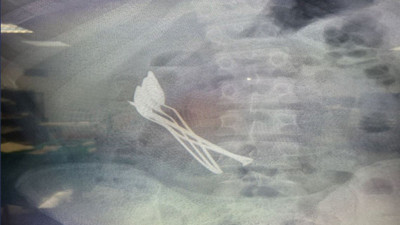

15 yaşındaki çocuğun midesinden 4 kaşık ve 1 çivi çıkarıldı Kayseri'de 15 yaşındaki erkek çocuğunun midesinden, 2 saat süren operasyonun ardından 4 metal tatlı kaşığı ve 1 çivi çıkarıldı.